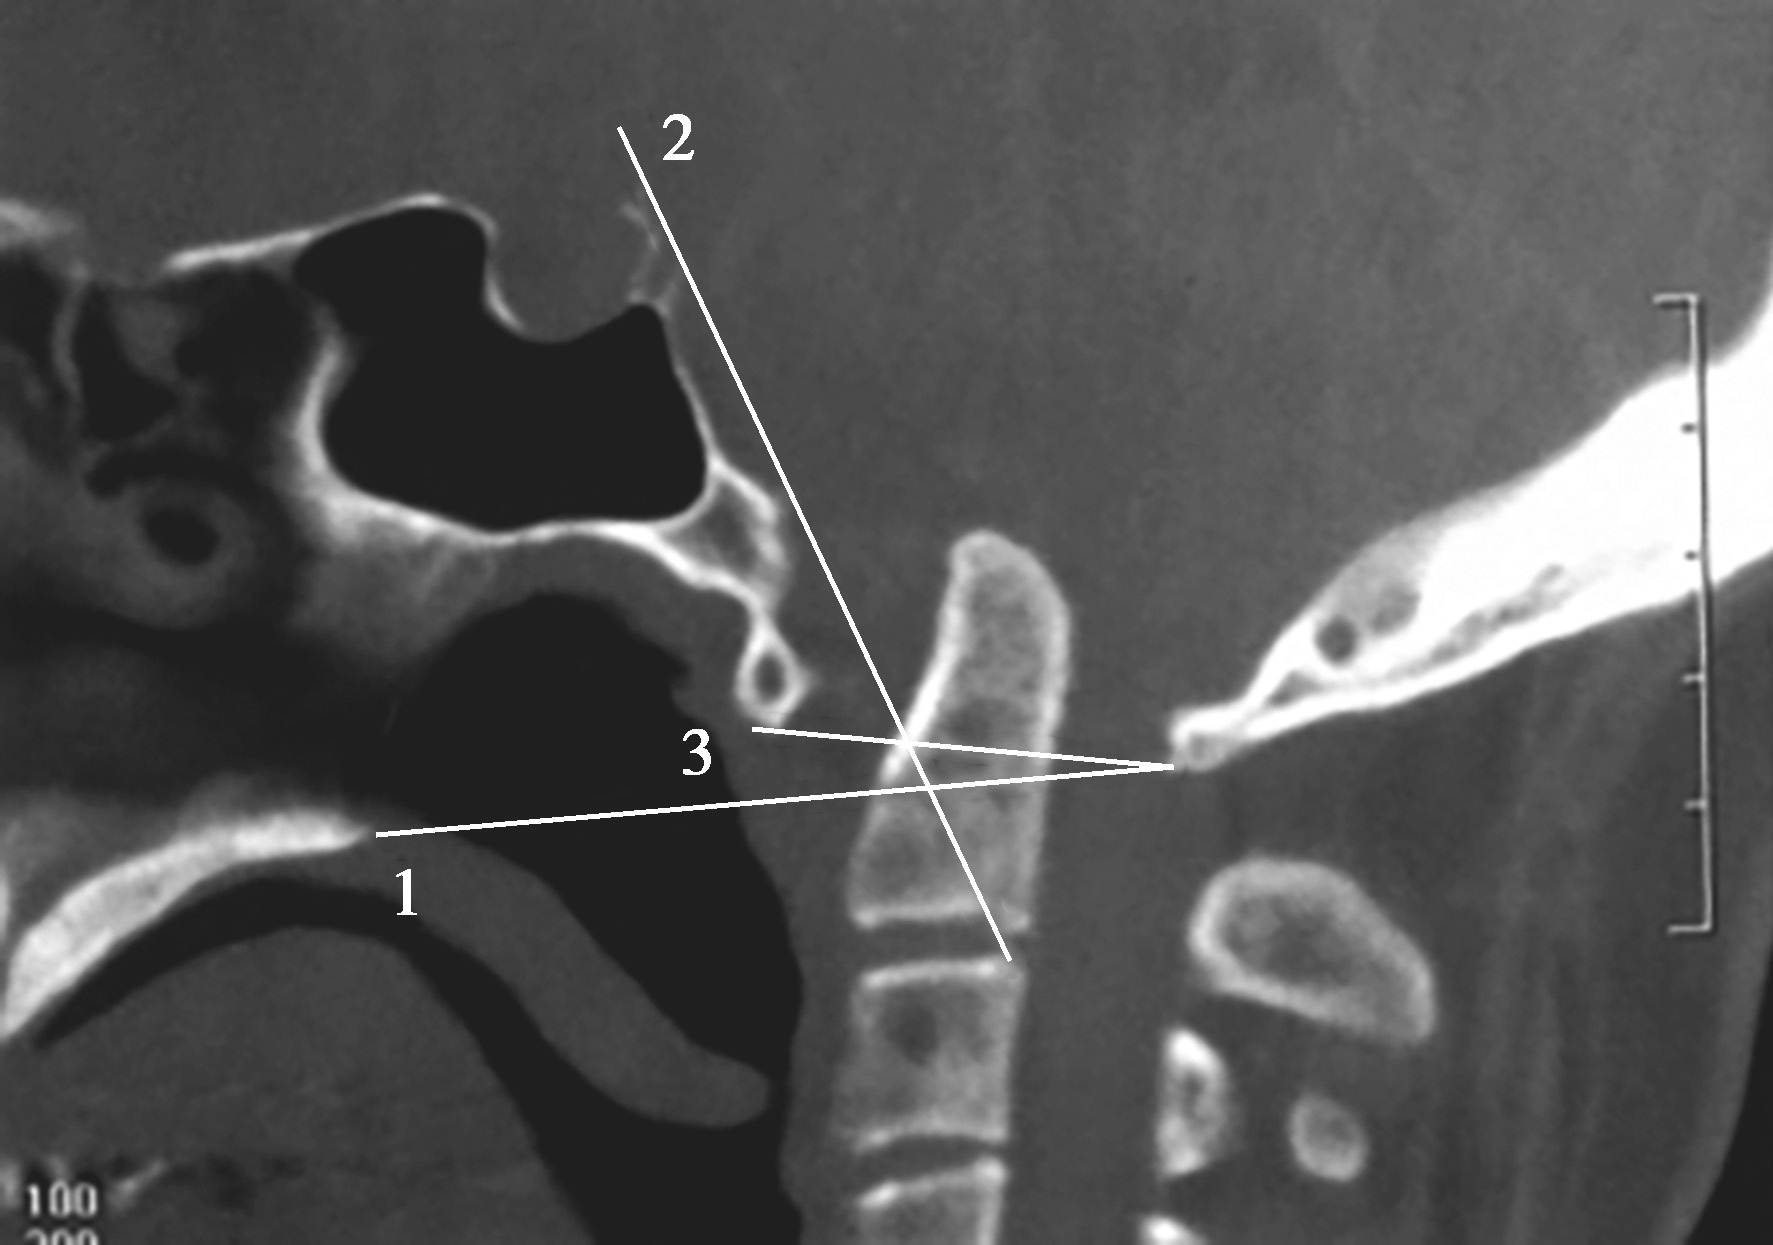

寰枕融合是指枕骨与寰椎部分或完全融合,寰椎成为枕骨的一部分,又可称之为寰椎枕化,可引发寰椎旋转与倾斜。同时也可能合并寰椎或枕骨与枢椎脱位、颅底凹陷及Chiari畸形和脊髓空洞等(图4-4-2、图4-4-3)。

图4-4-2 寰枕融合(一)

图4-4-3 寰枕融合(二)

寰椎后弓与枕骨融合,枢椎后弓与第三颈椎后弓融合,颅底凹陷,合并脊髓空洞。